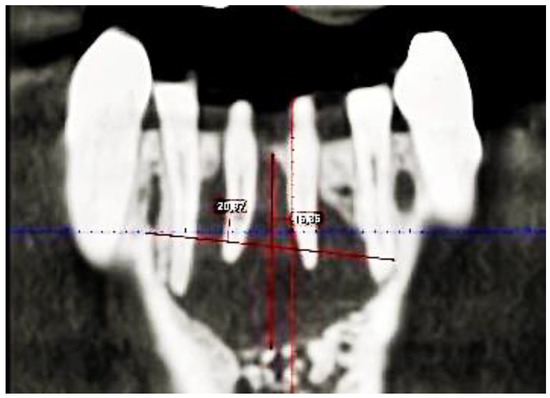

2. Case Description

3. Clinical Procedure and Outcome